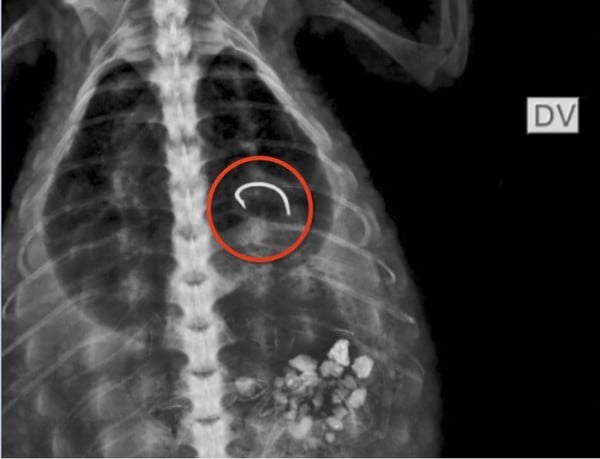

"Encontramos um anzol fixado na região do esôfago que não entrou no estômago. Dentro do estômago dele, o raio x apontou que há um conteúdo com densidade alterada e sinais de ossos. A suspeita é que alguém usou um caranguejo, pois vemos os ossos desse animal, como isca para tentar pescar o jacaré", explicou Natália Faria, veterinária.